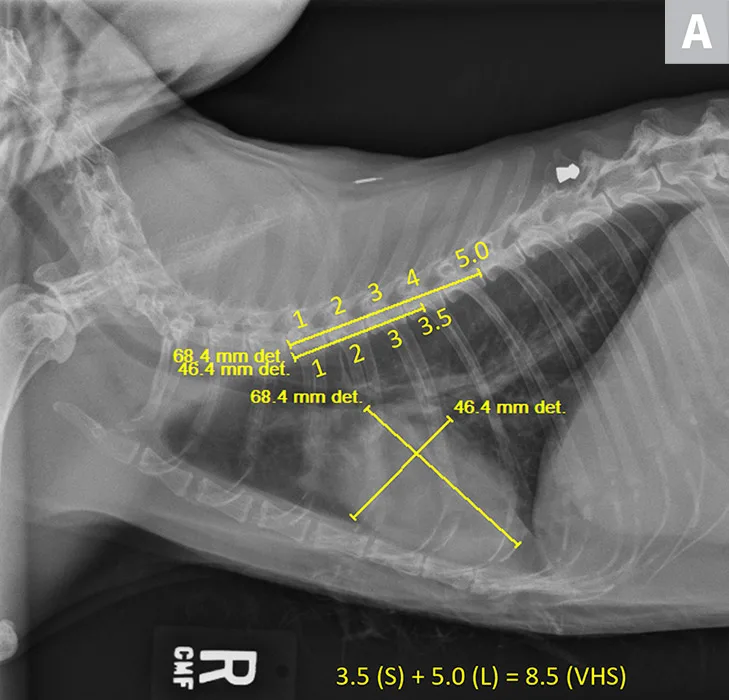

A 12-year-old neutered male domestic shorthair cat was presented for evaluation of a previously diagnosed heart murmur. On physical examination, a grade III-IV/VI left parasternal systolic murmur was auscultated. All other physical examination findings were within normal limits. There is history of right thoracic limb lameness and mild lytic lesions on the right humerus. Thoracic radiographs revealed mild to moderate cardiac silhouette enlargement with VHS 8.5, suggestive of cardiac disease (Figure 2). Additional cardiac diagnostic investigation (eg, total thyroxine, echocardiography) is recommended, and medical treatment should be considered.

VHS calculation in a cat diagnosed with HCM using a right lateral radiograph (A). L (ie, long axis; 5.0) is drawn from the carina to the most ventral aspect of the apex. S (ie, short axis; 3.5) is drawn perpendicular to L at the widest aspect of the heart, extending to the cranial and caudal borders. S and L are transposed along the spine from the cranial aspect of T4 using calipers. The number of vertebrae traversed (rounded to the nearest tenth) are summed to calculate VHS (8.5). Pulmonary vasculature is prominent but within normal limits, and there is a ballistic metallic foreign body (likely a bullet) in the dorsal subcutaneous tissue of the caudal thorax. Moderate spondylosis deformans exists at T13-L1 and L1-L2, and there is bridging spondylosis deformans at T10-T11. Intervertebral disk space at T10-T11 is collapsed, and there is fusion at the 2 vertebral bodies. Orthogonal radiograph of the patient is also shown for more complete evaluation of cardiac silhouette (B).